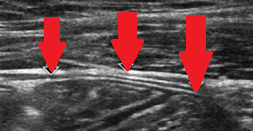

Ultrasound examination. Red arrows: Thickened peritoneum (Courtesy Dr. V. Penopoulos)